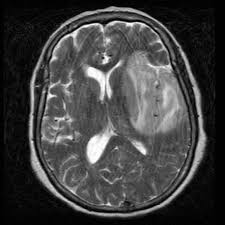

Brain Mri Scans Of A Patient With Acute Herpes Simplex Type 1 Download Scientific Diagram

Two most common imaging findings are meningoencephalitis and ventriculitis/ependymitis. Lumbar puncture showing isolated mild pleocytosis. Mri is the preferred imaging modality for hsv encephalitis. The clinical syndrome is often characterized by the rapid onset. Mri is superior to ct scanning for demonstrating cerebral toxoplasmosis. Encephalitis in the immunocompromised host. Due to lack of facilities. Herpes simplex encephalitis is a type of infectious encephalitis which happens when herpes simplex virus (hsv) enters the brain. Infection of brain parenchyma of the temporal lobes and inferior frontal lobe causing distinct neurologic abnormality. Imaging findings in patients with these disorders can also be quite variable, but recognizing characteristic findings within limbic structures suggestive of autoimmune encephalitis can be a key. Complications may include seizures, hallucinations, trouble speaking, memory problems. Encephalitis is an infectious or inflammatory disorder of the brain manifest by fever and headache and associated with a depressed level of consciousness, an altered mental status (confusion, behavioral. Encephalitis • usually hsv1 (hsv 2:

• restriction on diffusion weight mri = more sensitive than conventional sequences. Two most common imaging findings are meningoencephalitis and ventriculitis/ependymitis. Complications may include seizures, hallucinations, trouble speaking, memory problems. Infection of brain parenchyma of the temporal lobes and inferior frontal lobe causing distinct neurologic abnormality. Herpes simplex encephalitis (hse) is a rare neurological disorder characterized by inflammation of the brain (encephalitis).

Herpes simplex encephalitis occurs as 2 distinct entities: Herpes simplex encephalitis (hse) is a rare neurological disorder characterized by inflammation of the brain (encephalitis). Encephalitis • usually hsv1 (hsv 2: In cmv encephalitis, there is usually only non specific increased t2/flair signal in the white matter. Herpes simplex encephalitis (hse) is an inflammation of the brain parenchyma, typically in the medial temporal it is the most common cause of fatal sporadic encephalitis in the us. 2 435 просмотров 2,4 тыс. Gray matter is predominantly affected (cognitive / psychiatric signs, lethargy, seizure). • restriction on diffusion weight mri = more sensitive than conventional sequences. Management of hsv encephalitis in adults and neonates: Mri is superior to ct scanning for demonstrating cerebral toxoplasmosis. Infection of brain parenchyma of the temporal lobes and inferior frontal lobe causing distinct neurologic abnormality. Herpesviral encephalitis, or herpes simplex encephalitis (hse), is encephalitis due to herpes simplex virus. Herpes simplex encephalitis is a type of infectious encephalitis which happens when herpes simplex virus (hsv) enters the brain.